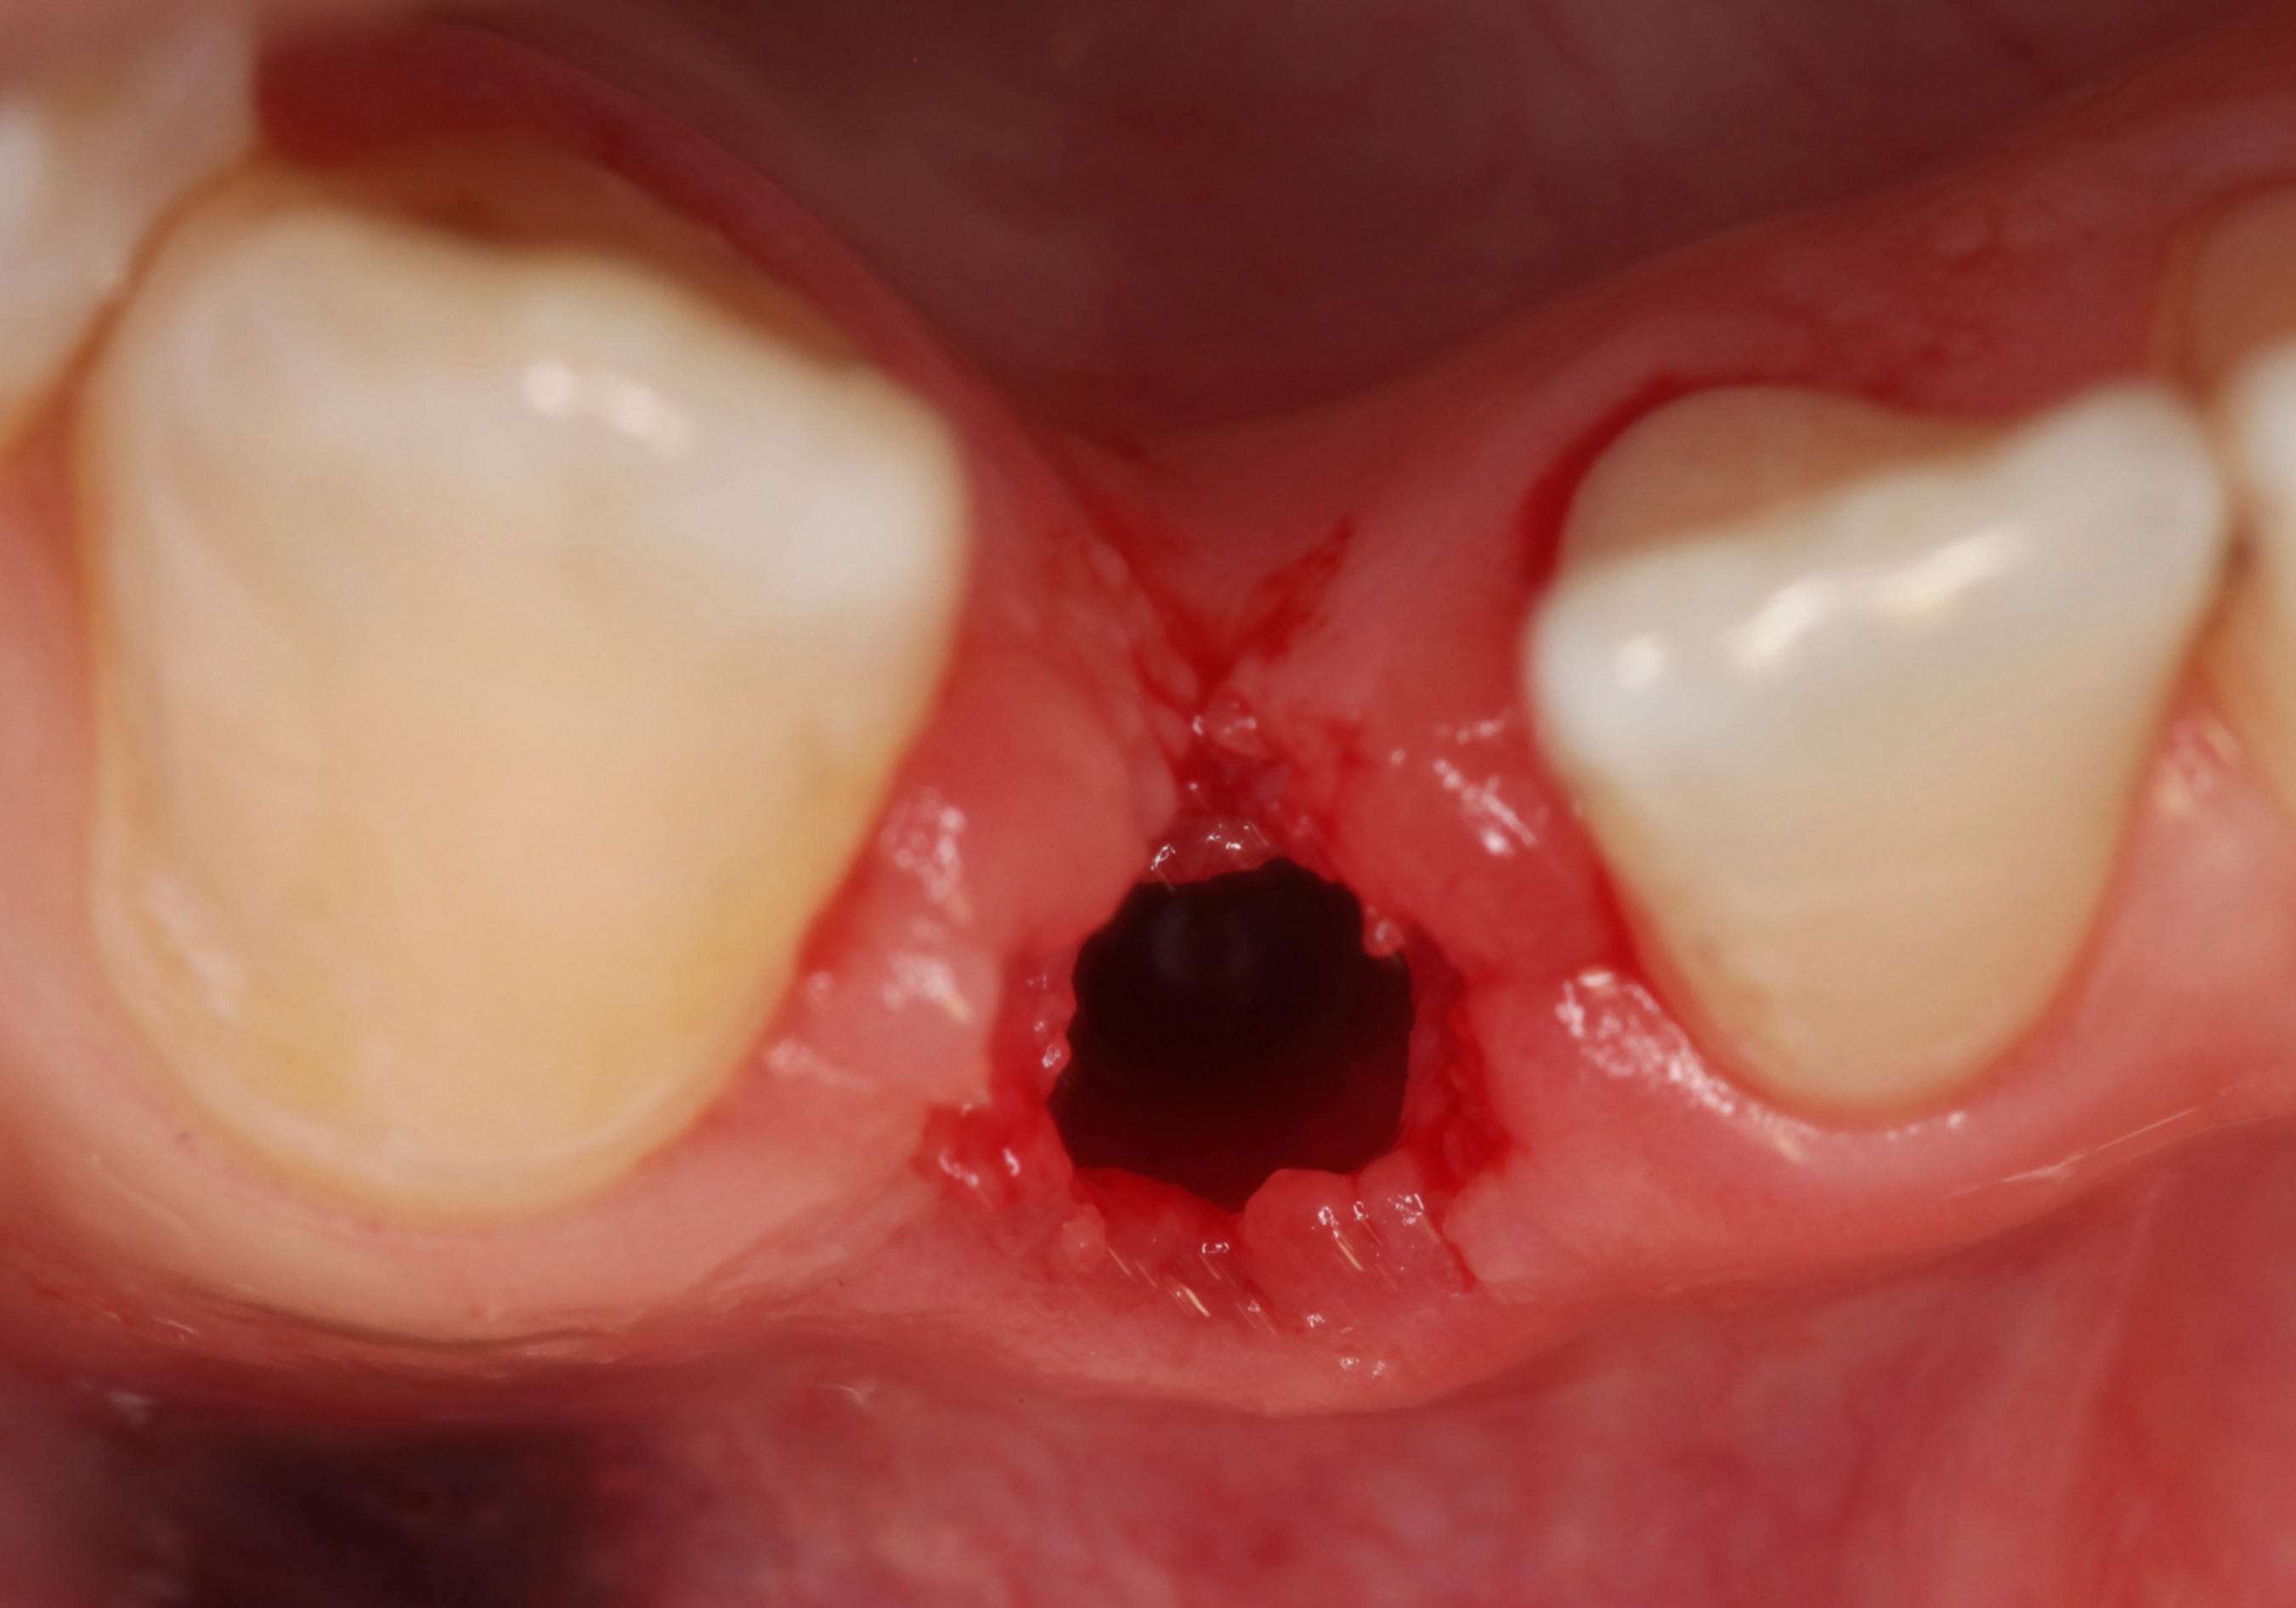

The following case report provides an example of this case scenario: A 24-year-old white male presented with congenitally missing tooth No. 26 restored with a single-tooth cement-retained implant restoration. The implant was placed excessively to the facial aspect of the edentulous site and too shallow, and the periodontal phenotype was thin scalloped (Figure 32). In an effort to mimic the lost midfacial soft tissues, pink ceramics were used as a cosmetic facade. Even though the restoration was not in the esthetic zone, the patient was highly displeased with the esthetic outcome and sought remediation.

The crown and screw-retained custom abutment were removed, and a surgical cover screw was placed into the implant, thereby allowing spontaneous gingival augmentation in situ (Figure 33 and Figure 34). Note that the lingual aspect of the implant site was significantly more coronal than the labial aspect, which was positive because the defect would be limited to a facial–lingual defect. A fixed RBR bridge was cemented on the adjacent teeth and used as a tooth-supported transitional provisional restoration (Figure 35). A few weeks were allotted to let the soft tissue heal and migrate around the cover screw (Figure 36) to see if there would be complete coverage, thereby allowing a soft-tissue augmentation procedure to be performed with primary flap closure as in clinical scenario No. 2. The major obstacle in achieving a positive tissue response was that the implant depth was also deficient because the implant–abutment connection was at the level of the free gingival margin. It was decided that the best treatment option would be to remove the implant. A high-powered reverse-torque device (Fixture Remover Kit, NeoBiotech, www.neobiotechus.com) was used to remove the implant atraumatically (Figure 38 through Figure 41). The implant socket was allowed to heal for several months not unlike an extracted tooth (Figure 42). A new implant was placed in a better position from both a restorative and esthetic perspective (Figure 43), and after a few months of healing, a new crown was made (Figure 44). A satisfactory functional and esthetic result was achieved (Figure 45 and Figure 46) without employing pink porcelain.